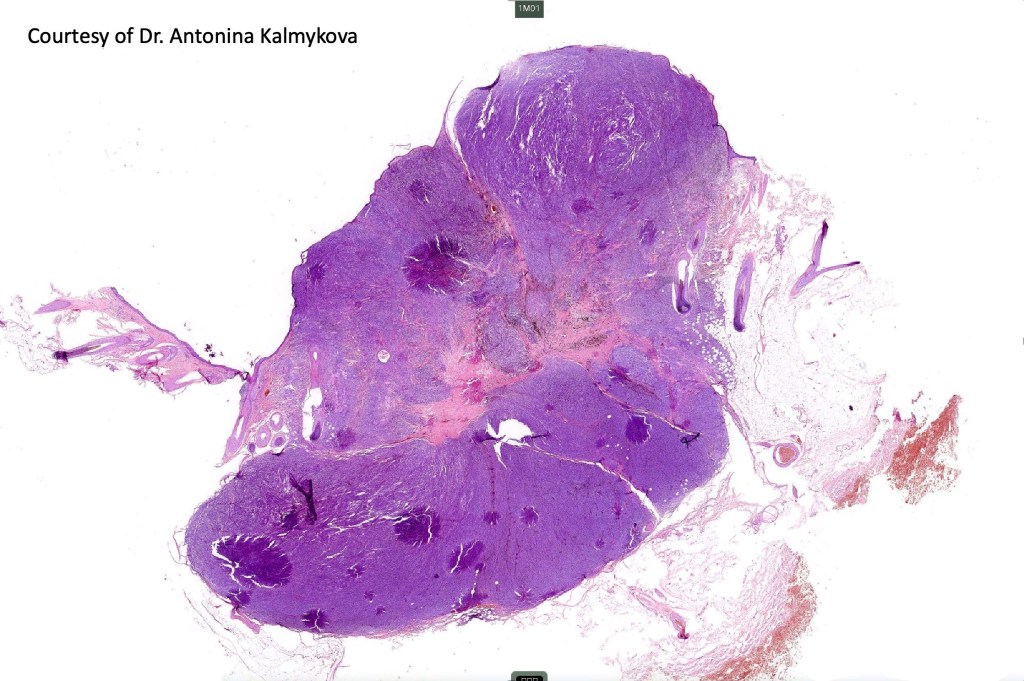

Histological features

•Develops within a precursor lesion as one or more nodules of epithelioid or spindled cell melanoma

•Or melanoma showing admixed blue nevus-like features (dendritic cells and melanophages) in the absence of a precursor lesion

•The latter may show a dumbbell appearance at low power or scanning magnification